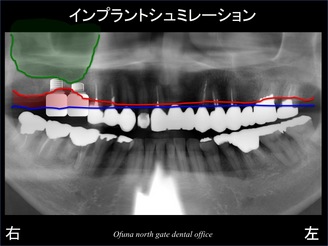

いつものように 骨吸収の状態を分かりやすくするために 骨吸収の状態を線で書いたのが以下のレントゲンになります。

青線が骨吸収を起こす前の骨の位置です。

赤線は、現在の骨の位置です。

緑線は上顎洞です。

上顎洞(緑線の上方)は空洞です。

骨ではなく、穴が開いているのです。

以下のレントゲンは、

上顎洞(空洞部分)を緑色、

骨吸収した部位を赤色であらわしたものです。

現在残っている骨は、緑色と赤色の間のみになるのです。

骨がかなり吸収しているのが分かるかと思います。